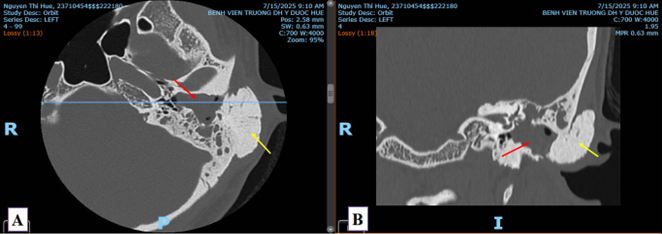

Bệnh nhân nam 77 tuổi, tiền sử ung thư trực tràng đã đã phẫu thuật, đang điều trị hoá chất, vào viện vì triệu chứng đau hai chân, đi lại khó khăn. Thăm khám lúc vào viện ghi nhận bệnh nhân tỉnh táo, sinh hiệu ổn (mạch 60 lần/phút, huyết áp 130/80 mmHg), đau kèm tê hai chân, không thấy sưng nóng đỏ, có đau cách hồi rõ, mạch đùi còn bắt rõ, mạch mu chân không bắt được, không thấy loét hay hoại tử khô đặc biệt ở các ngón. CT toàn thân cho thấy tổn thương thứ phát đa ổ trên nền tổn thương viêm xơ giãn phế quản khắp hai phổi, chưa thấy tổn thương nghi tái phát hay thứ phát trong ổ bụng. Trên CLVT mạch máu (CT angiography) thấy xơ vữa vôi hoá lan toả động mạch chủ bụng và động mạch chậu hai bên, gây hẹp nặng khẩu kính động mạch chậu chung hai bên #90% (Hình 1). Tổn thương xơ vữa lan đến động mạch chậu trong, chậu ngoài hai bên và các nhánh. Xơ vữa vôi hoá gây hẹp từng đoạn hệ động mạch chi dưới nhiều mức độ, khoảng 50-70%. Chưa thấy tổn thương thâm nhiễm, loét mô mềm chi dưới hai bên.

Hình 1. Hình ảnh cắt lớp vi tính mạch máu (CTA) mặt phẳng axial (A, B), tái tạo MIP (C) và VRT (D): Tổn thương xơ vữa vôi hoá lan rộng ở đoạn cuối động mạch chủ bụng, động mạch chậu chung, chậu trong, chậu ngoài hai bên, gây hẹp nặng khẩu kính (mũi tên).